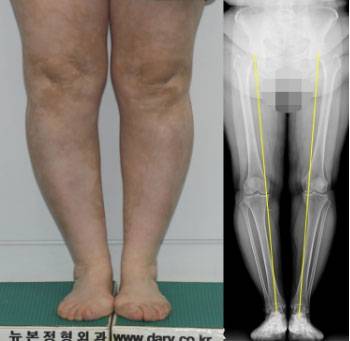

| 내반슬(오다리)인데 다리가 붙은 환자

반대로 내반슬, 즉 수술 전에 뼈 모양은 오다리 상태인데 무릎이 붙어 있는 환자들도 존재한다. 비교적 다리에 살이 많은 사람들이 이 경우에 해당된다.

이런 환자는 대개 무릎 통증 때문에 찾아오는데 통증을 없애려면 엑스다리를 만들어야 하는 불가피한 선택에 놓이게 된다. 엑스다리가 되더라도 통증을 없앨 것이냐? 통증을 참고 견디며 미용적인 것을 사수할 것이냐? 대개는 통증을 없애는 쪽으로 의견이 기운다.